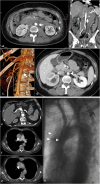

Objectives: To demonstrate the various presentations of acute aortic pathology and to present diagnostic and therapeutic approaches.

Methods: Diagnostic imaging is the key to the reliable diagnosis of acute aortic pathology with multi-slice computed tomography angiography (CTA) as the fastest and most robust modality. Endovascular aortic repair (EVAR) with stent grafts and open surgical repair are therapeutic approaches for aortic pathology.

Results: CTA is reliable in diagnosing and grading aortic trauma, measuring aortic diameter in aortic aneurysms and detecting vascular wall pathology in acute aortic syndrome and aortic inflammation. CTA enables planning the optimal therapeutic approach. Stent graft implantation and/or an open surgical approach can address vascular wall pathology and exclude aortic aneurysms.

Conclusion: Aortic emergencies have to be detected quickly. CTA is the imaging method of choice and helps to decide whether elective, urgent or emergent treatment is necessary with EVAR and open surgical repair as the main treatment approaches.

Teaching points: • To present aortic pathology caused by trauma • To present acute aortic syndrome (aortic dissection, intramural haematoma and penetrating ulcers) • To present symptomatic and ruptured aortic aneurysm • To present infection (mycotic aneurysms/aorto-duodenal fistulae) or iatrogenic injury of the aorta • To understand different presentations for treatment planning (EVAR and open surgery).